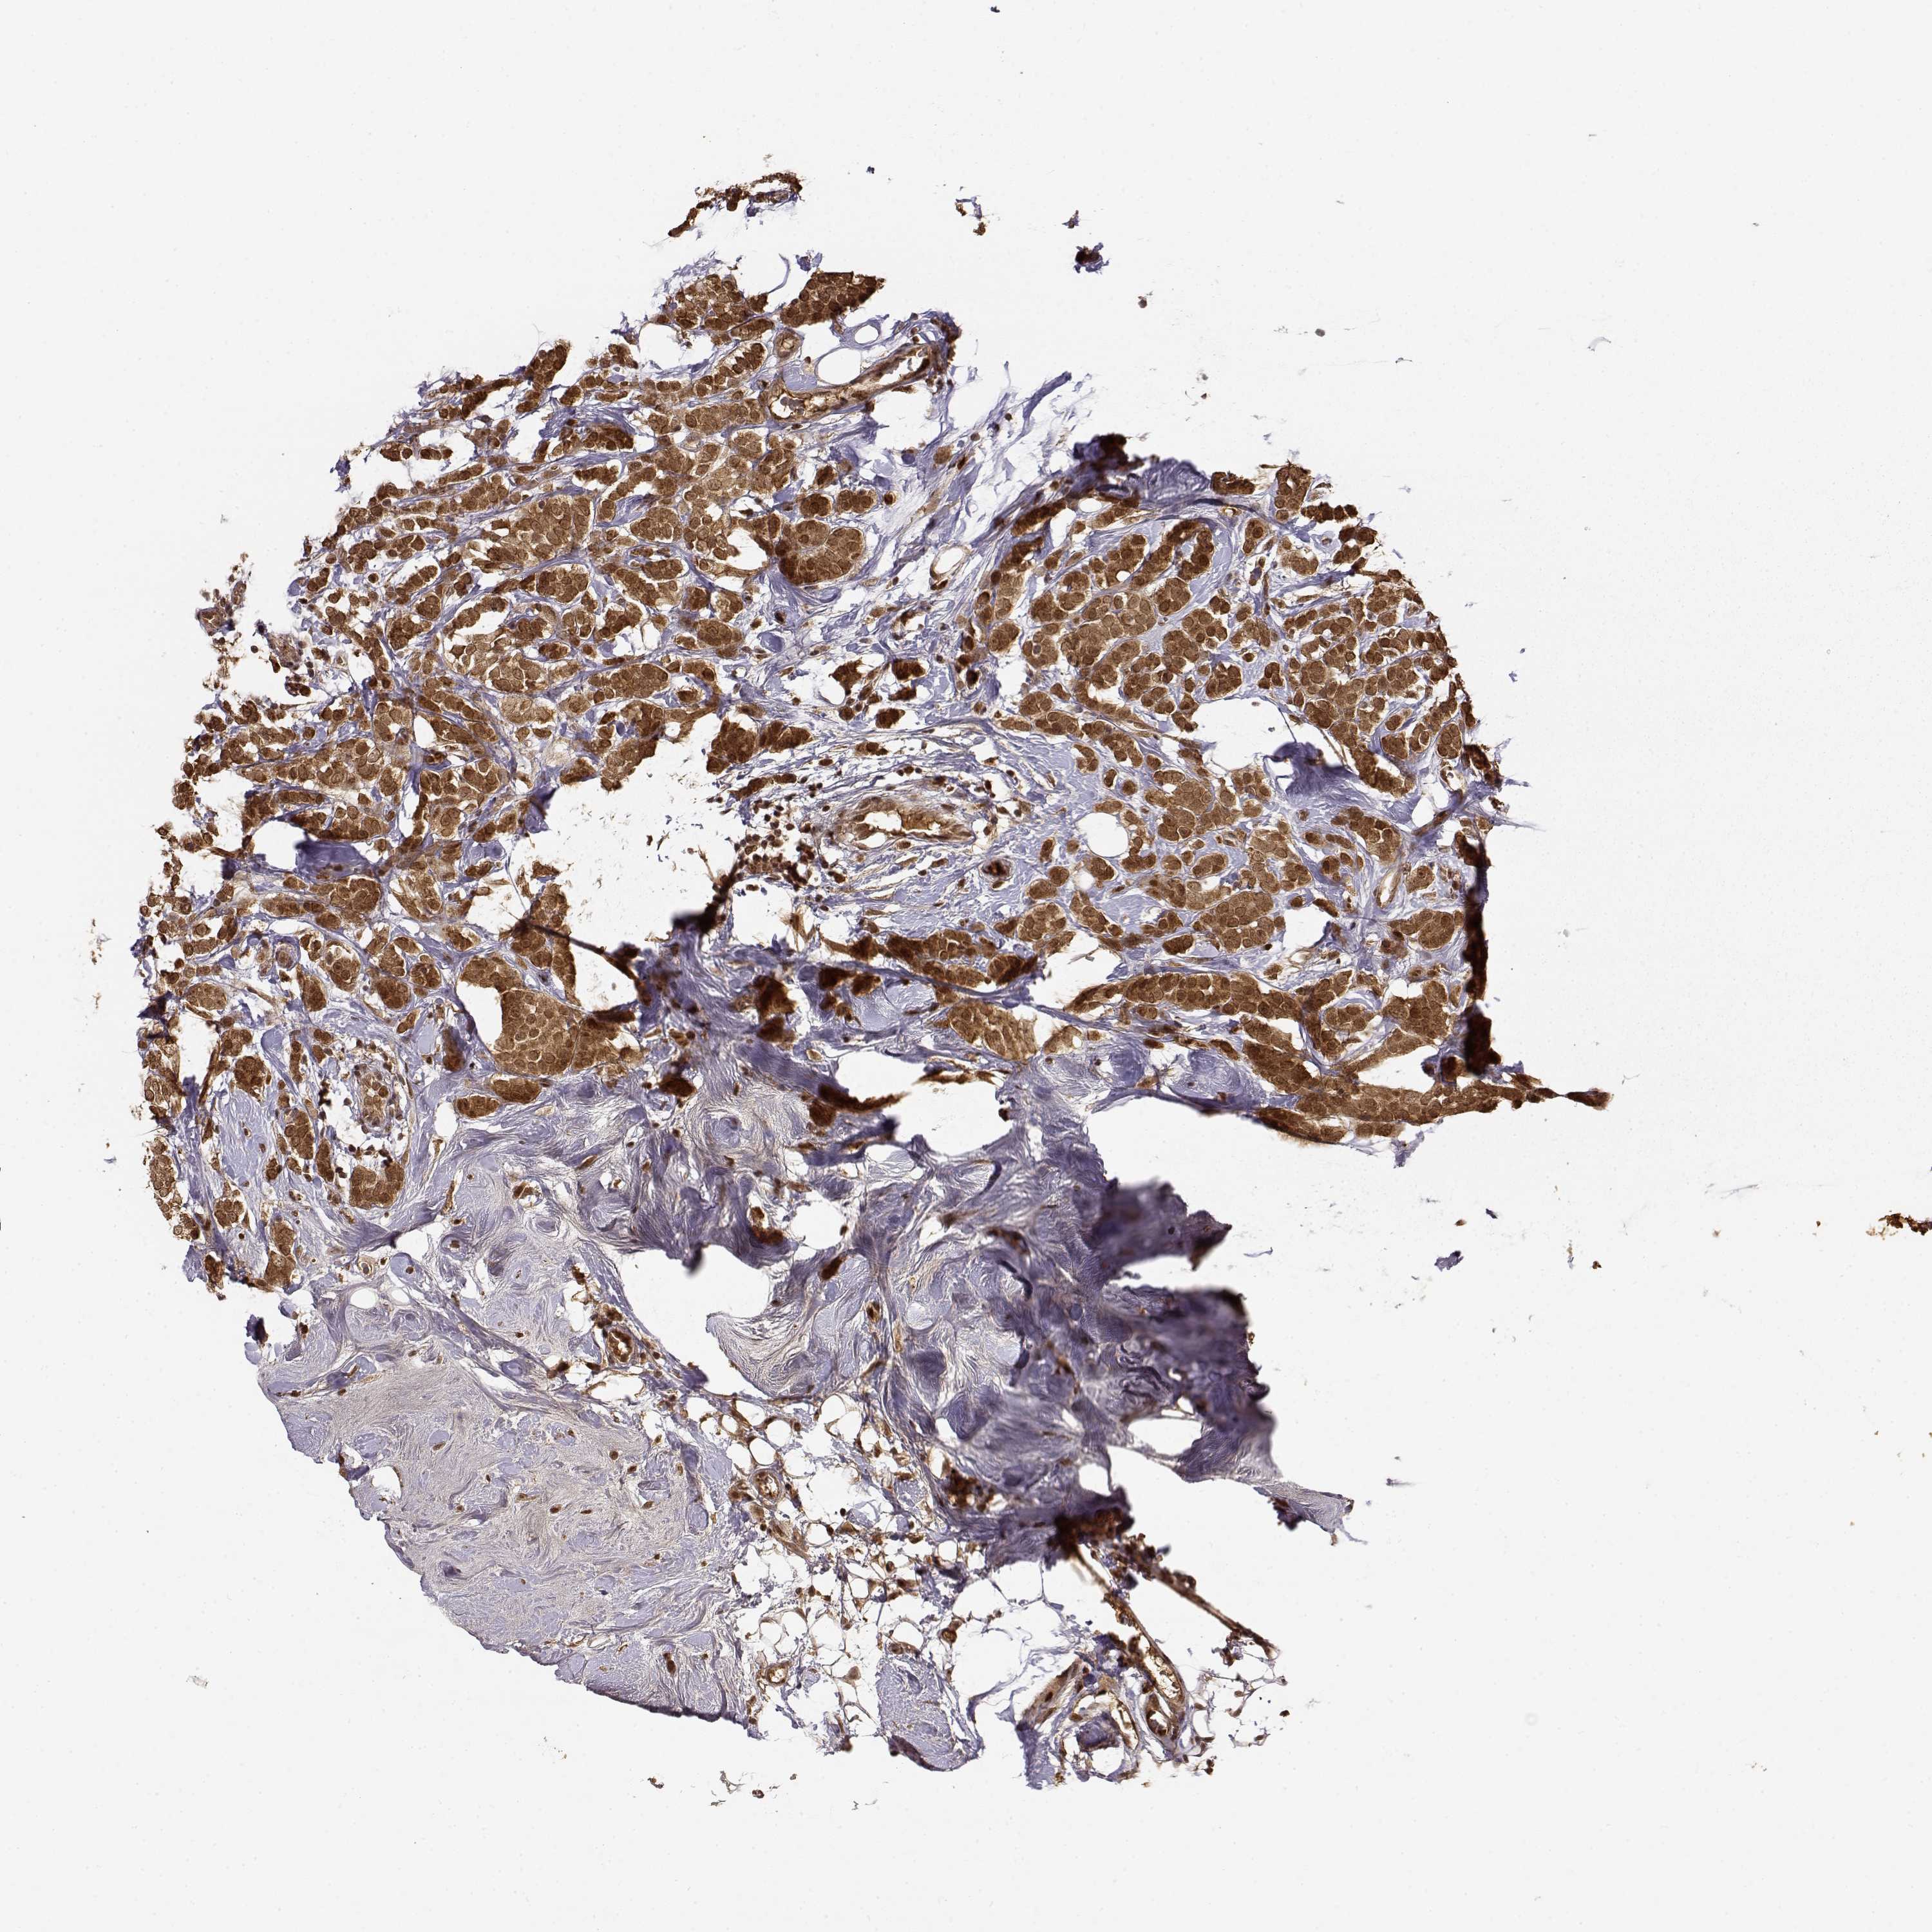

CANCER BREAST CANCER Show tissue menu

BRCA TCGA BRCA VALIDATION PROTEIN EXPRESSION